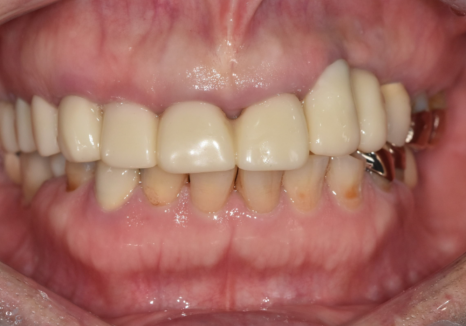

임플란트 식립 2개월 뒤,

뼈와 완벽히 굳은 것을 확인하고

지르코니아 보철로 마무리를 해드렸습니다.

주변 치아와 구분되지 않을 만큼

자연스러운 색상과 배열로

완성된 모습을 보시고

환자분께서도 매우 만족해하셨습니다. ^^